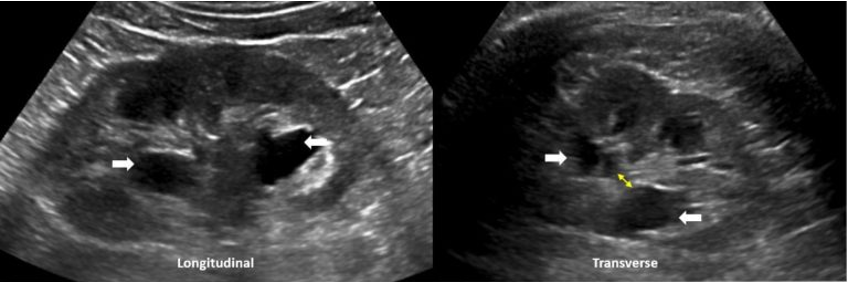

POCUS findings:

Dilated renal pelvis with multiple coalescing, anechoic calyces and parenchymal thinning, consistent with severe hydronephrosis bilaterally — new on the left, with more cortical thinning noted on the right. The bladder (not shown here) was fully decompressed.

**Both of this patient’s kidneys appear to have grade 4 or severe hydronephrosis based on ultrasound.